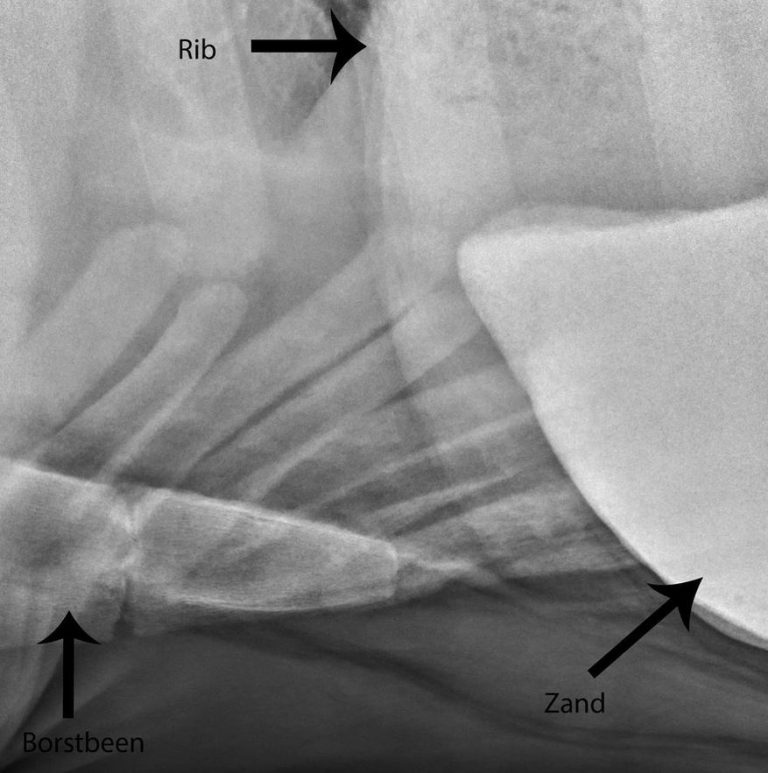

De oorzaken van echte koliek bevinden zich wél in het maag-darmkanaal. De meest voorkomende oorzaken zijn verstopping door zand (zie afbeelding), kramp, obstipatie of gasophoping.

Zandkoliek bij het paard